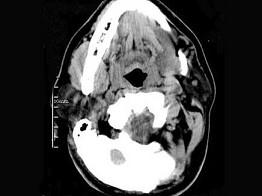

问题 男,32岁,左侧下颌部肿块,CT如图所示,最可能的诊断是 ( )

选项 A、颈部淋巴管瘤 B、舌下腺囊肿 C、颌骨囊肿 D、鳃裂囊肿 E、造釉细胞瘤

答案 B